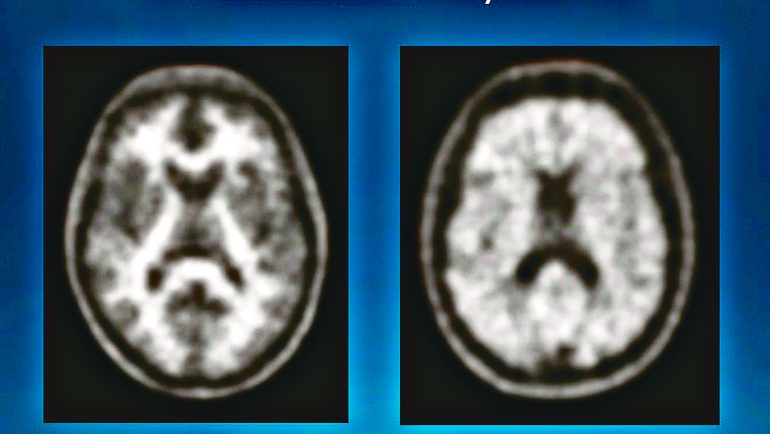

類澱粉蛋白正子造影檢查,圖左為正常的大腦影像,圖右顯示腦內充斥類澱粉蛋白。(聯新國際醫院提供) 記者陳華興∕桃園報導 一名65歲男性退休後逐漸出現記憶力與學習障礙,檢查發現左側丘腦有血管栓塞,進一步透過類澱粉蛋白正子造影(PET-CT)確診為阿茲海默症。醫師指出,此類病症初期常與老化混淆,若未及早辨識,恐延誤治療時機。 聯新國際醫院神經內科主任林衛邑說明,阿茲海默症是失智症最常見的原因,病理機轉與類澱粉蛋白及濤蛋白的異常沉積密切相關,其初期表現即為記憶力喪失。這些蛋白原本應被清除,卻因腦部出現許多問題而導致過度堆積,逐漸破壞神經功能,造成認知衰退。 林衛邑表示,阿茲海默症雖然病理特徵明確,治療上目前主流的口服藥物如「膽鹼酯酶抑制劑」與「NMDA受體阻斷劑」僅適用於阿茲海默症,「膽鹼酯酶抑制劑」亦可適用於帕金森病失智症,其藥理作用分別為提高腦中乙醯膽鹼濃度與延緩神經細胞衰亡速度,讓認知功能退化的速度趨緩。 醫師林衛邑說明提早清除類澱粉蛋白藥物,為阿茲海默症患者爭取黃金時間延緩退化。(聯新國際醫院提供) 林衛邑指出,今年引進的類澱粉蛋白單株抗體注射劑,則是專為類澱粉蛋白沉積所導致的失智症設計,不適用於路易氏體失智症、額顳葉失智症等類型患者的治療。施打前須先經過類澱粉蛋白正子造影確認病因,且僅限CDR評估為0.5~1分的輕度患者使用。治療前需先接受腦部磁振造影掃描,並安排住院注射與定期磁振造影追蹤以監測腦出血或腦水腫等併發症,整個療程達1年半。 國衛院呼籲,40歲起為失智預防黃金期,提出「顧腰圍、控血糖、壓不衝、脂不高、腎要好」5大護腦守則。林衛邑也提醒,三高、肥胖、抽菸與缺乏運動都是加速類澱粉蛋白堆積,提高失智風險的主因。 遠離失智多採用地中海飲食。(聯新國際醫院提供) 林衛邑建議多運動、多動腦、保持活躍心智以提升「認知儲備」,採行地中海飲食、控制三高、遠離含糖飲料,維持良好生活習慣以降低失智風險,若有疑慮則應及早就醫篩檢。早期發現、積極治療與矯正危險因子才能延緩退化,爭取更多時間與提升生活品質。